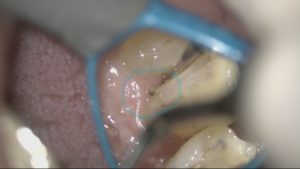

こちらの写真は顕微鏡で拡大したもの

下の前歯です🦷歯と歯ぐきの縁の部分に風をかけてみると…

歯ぐきが、ぺらっと広がり

歯と歯ぐきの溝に汚れが溜まっていることが確認できました。

健康な歯ぐきは引き締まって歯に付着しているため、このような広がり方はしません!

これらの内容を理解していただいた上で治療へ進みます。そんな時に今のお口の状態を拡大した動画や静止画で見ていただくことができます。

こちらはクリーニング前後の写真です。